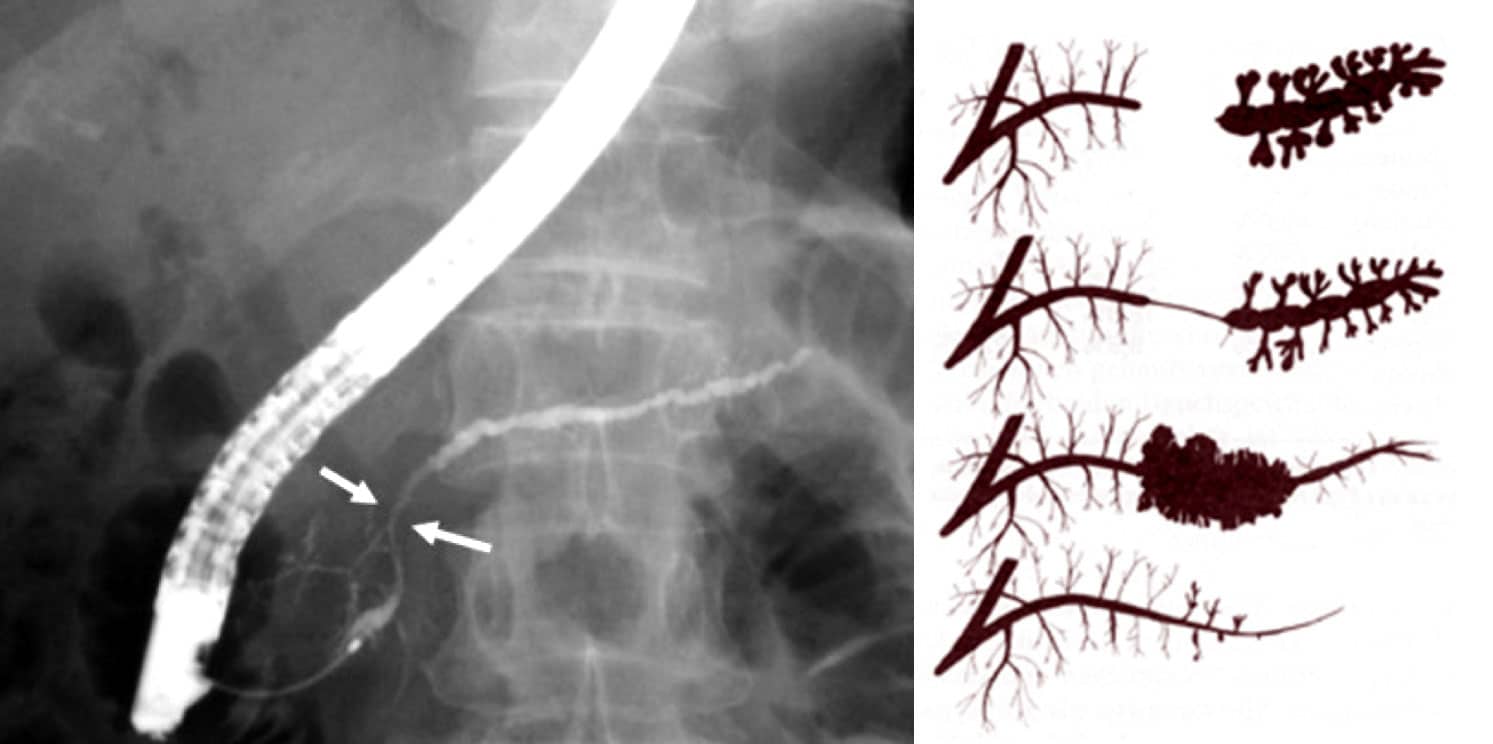

Εφόσον αρχικά σκιαγραφείται ο παγκρεατικός πόρος, συνεχίζεται η έγχυση υπό ακτινοσκόπηση με μικρό πεδίο. Συνήθως επαρκούν 2 ml σκιαγραφικού υλικού για την πλήρη σκιαγράφηση του μείζονος παγκρεατικού πόρου. Μόλις πληρωθεί ο παγκρεατικός πόρος μέχρι την ουρά του παγκρέατος, σταματά η έγχυση, γιατί τότε στην ανατομική περιοχή της κεφαλής θα έχουν πληρωθεί και οι παράπλευροι κλάδοι, οι οποίοι απεικονίζονται ευκρινώς στην ακτινογραφία. Προσέχουμε ιδιαίτερα να μη σκιαγραφηθεί το παρέγχυμα, γιατί αυξάνεται ο κίνδυνος της μετά ERCP παγκρεατίτιδας.

Χρησιμοποιούνται ακτινολογικά φίλμ διαστάσεων 24 Χ 30 cm και προτιμάται η τμηματική λήψη τεσσάρων διαδοχικών εικόνων σ’ ένα φιλμ. Αρχικά, απεικονίζεται η κεφαλή, μετά το σώμα, στη συνέχεια η ουρά και τελευταία για άλλη μια φορά η περιοχή της κεφαλής, επειδή στο μεταξύ θα έχουν σκιαγραφηθεί και οι παράπλευροι κλάδοι πρώτης και δεύτερης τάξης.

Οι κύριες ενδείξεις της διαστοματικής χολαγγειοσκόπησης είναι τα διφορούμενα ακτινολογικά ευρήματα που αναδεικνύονται με την ERCP και οι δύσκολες περιπτώσεις λιθίασης των χοληφόρων, που δεν αντιμετωπίζονται επιτυχώς με τους γνωστούς ενδοσκοπικούς τρόπους. Συνήθεις περιπτώσεις αποτελούν οι στενώσεις και τα σκιαστικά ελλείμματα των χοληφόρων αγγείων, η φύση των οποίων δεν μπορεί να διαλευκανθεί με τη διαγνωστική ERCP

Η διαφοροδιάγνωση των σκιαστικών ελλειμμάτων που αναδεικνύονται στην ERCP, γίνεται ευχερώς με την χολαγγειοσκόπηση. Ένα σκιαστικό έλλειμμα ενδέχεται να είναι λίθος, καλοήθης όγκος ή ένα καρκίνωμα των χοληφόρων με πολυποειδή ανάπτυξη. Η διαγνωστική τεκμηρίωση των καλοηθών όγκων γίνεται μόνο ιστολογικά με την λήψη ιστοτεμαχιδίων με λαβίδα βιοψίας ή μετά την αφαίρεση με βρόχο πολυπεκτομής .